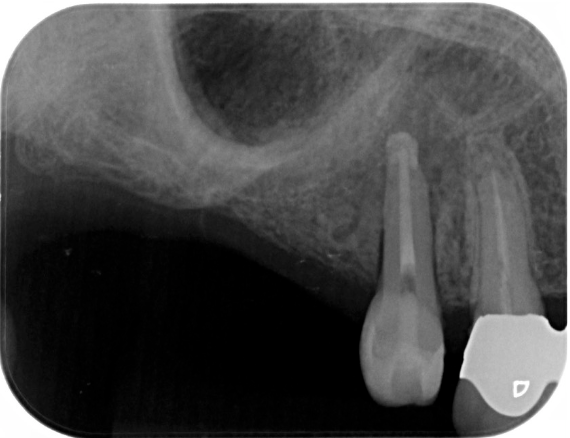

症例3

| 項目 | 詳細 |

|---|---|

| 患者様データ | 68歳 女性 |

| 来院時の主訴 | 「普通に食事がしたい。」 |

| 医院の診断 | 歯牙欠損、重度の顎堤欠損、角化歯肉不足 |

| 通院期間 | 10か月 |

| 来院回数 | 15回 |

| 治療費 | 総額:1,005,000円(税抜) 【内訳】 GBR(骨再生手術)250,000円、インプラント埋入手術250,000円、2次手術+FGG(遊離歯肉移植術)55,000+60,000円、仮歯30,000円、インプラント上部構造(セラミッククラウン)170,000円、歯冠長延長術70,000円、セラミッククラウン120,000円 |

| リスクと副作用 | 定期的なメンテナンスが必要、術後若干の腫れと痛み |

| ここがこだわりのポイント!☝ | 骨量不足により他院にてインプラントを断られた患者様です。大規模な骨造成を行うことでインプラント治療が可能になりました。 |